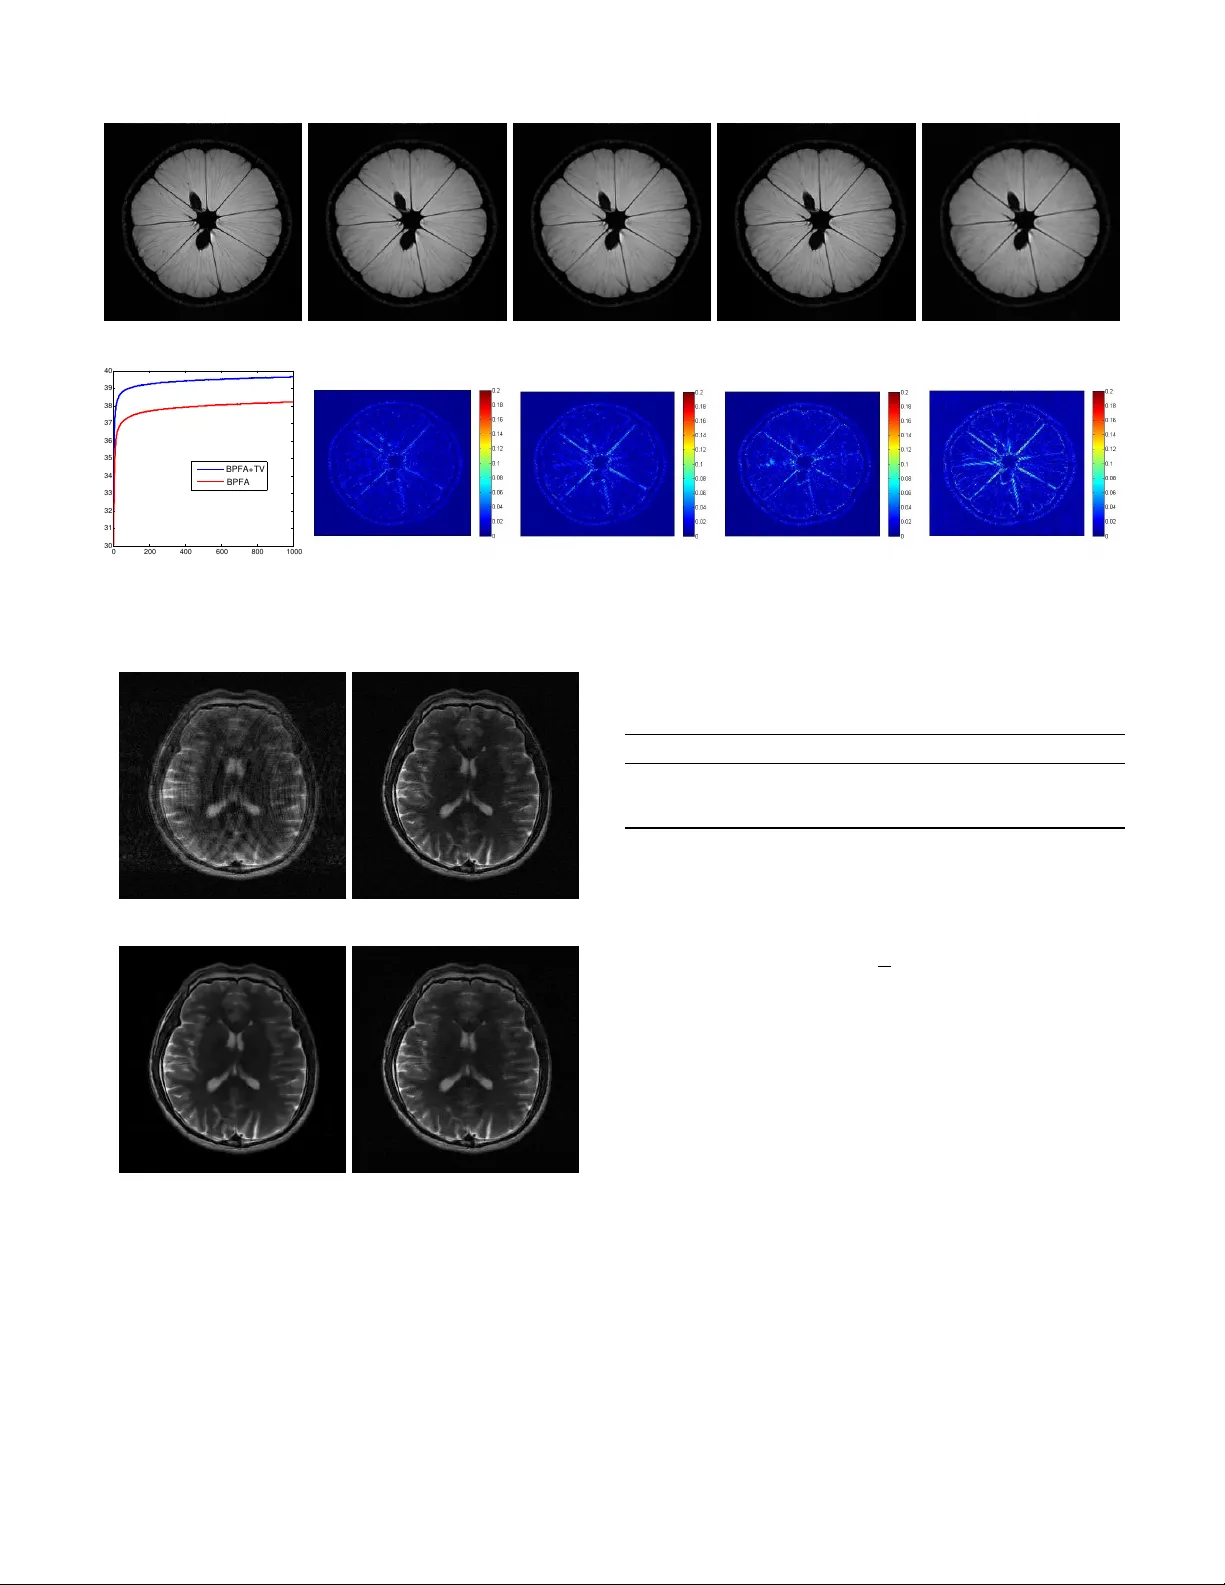

본 논문은 압축감지(MRI) 재구성에서 이미지의 희소성을 효과적으로 활용하기 위해 베타 프로세스(Beta Process)를 사전으로 하는 비모수 딕셔너리 학습 모델(BPFA)을 도입한다. 기존 CS‑MRI 방법은 전역 변환(웨이브렛, 컨투얼렛 등)이나 고정된 딕셔너리(K‑SVD)를 사용해 패치 수준의 희소성을 강제했지만, 이러한 접근은 딕셔너리 크기와 패치당 사용 원소 수와 같은 하이퍼파라미터를 사전에 설정해야 하며, 설정이 부정확하면 복원 품질이 크게 저하되는 단점이 있다. 베타 프로세스는 무한히 많은 잠재 요인(딕셔너리 원소)을 가정하고, 각 원소가 사용될 확률 π_k를 베타 분포로 모델링한다. 실제 데이터에서는 대부분의 π_k가 매우 작아 해당 원소가 거의 사용되지 않으며, 데이터가 필요로 하는 원소만이 높은 π_k를 갖게 된다. 이를 통해 딕셔너리 크기를 사전에 고정하지 않아도 되며, 데이터에 맞춰 자동으로 “프루닝”된다. 패치 i에 대한 표현은 α_i = s_i ∘ z_i 로 정의한다. 여기서 s_i는 가우시안(연속형) 가중치 벡터이며, z_i는 베르누이(이진) 마스크이다. z_i의 각 원소 z_{ik}는 π_k에 따라 베르누이 샘플링되므로, 패치마다 서로 다른 희소성 패턴이 자연스럽게 형성된다. 패치 재구성 손실은 (γ_ε/2)||R_i x – D α_i||^2 로 표현되며, γ_ε는 노이즈 정밀도(역분산)이다. 전체 목표 함수는 로컬 딕셔너리 손실, 전역 TV 정규화, 그리고 데이터 적합 항을 포함한다. 구체적으로  min_{x,ϕ} λ_g TV(x) + Σ_i (γ_ε/2)||R_i x – D α_i||^2 + f(ϕ_i) + (λ/2)||F_u x – y||^2 를 최적화한다. 여기서 f(ϕ_i)는 베타 프로세스 모델에 대한 사전 로그가능도이며, ϕ_i는 {D, s_i, z_i, γ_ε, γ_s, π}를 포함한다. 최적화는 두 부분으로 나뉜다. (1) 딕셔너리와 계수( D, s_i, z_i, γ_ε, γ_s, π )는 Gibbs 샘플링을 이용한 MCMC로 사후분포를 추정한다. 베타-베르누이 구조 덕분에 각 변수의 조건부 분포가 표준 형태(정규, 감마, 베타)로 나타나 효율적인 샘플링이 가능하다. (2) 이미지 x와 전역 TV 항은 ADMM을 적용해 별도 서브문제로 해결한다. ADMM은 x‑업데이트(데이터 적합 + TV 라그랑주 항)와 TV‑업데이트(소프트-쓰레시홀드)로 분리되어 빠른 수렴을 보인다. 실험에서는 4배~8배 언더샘플링된 k‑space 데이터를 사용해 여러 실제 MRI 데이터셋(뇌, 무릎, 심장 등)을 평가하였다. 비교 방법으로는 Sparse MRI(웨이브렛+TV), K‑SVD 기반 CS‑MRI, 그리고 BPFA 단독 디노이징을 포함한다. 결과는 다음과 같다. 1. PSNR 및 SSIM 측면에서 BPFA+TV가 모든 테스트 케이스에서 최고 성능을 기록했다. 특히 높은 노이즈 레벨(σ=30)에서도 K‑SVD은 파라미터 미스매치로 성능이 급격히 떨어지는 반면, BPFA는 자동으로 적절한 희소성 수준을 추정해 안정적인 복원을 제공했다. 2. 딕셔너리 사용 확률 π_k와 패치당 활성 원소 수를 시각화한 결과, 전체 K=108 중 실제로 사용된 원소는 약 80~100개에 불과했으며, 대부분의 패치는 2~4개의 원소만을 사용했다. 이는 베타 프로세스가 데이터 복잡도에 맞춰 적절한 희소성을 자동으로 조절함을 의미한다. 3. 전역 TV와 결합함으로써 경계 보존과 평탄 영역의 잡음 억제가 동시에 이루어졌으며, TV 파라미터 λ_g에 대한 민감도도 기존 방법보다 낮았다. 이는 딕셔너리 학습 자체가 강력한 디노이징 효과를 제공하기 때문이다. 논문의 주요 기여는 다음과 같다. - 비모수 베타 프로세스를 이용해 딕셔너리 크기와 패치별 희소성 패턴을 데이터로부터 자동 추정, 파라미터 튜닝 부담 감소. - MCMC 기반 베타‑베르누이‑가우시안 계층 모델을 설계하고, 이를 ADMM과 결합해 효율적인 CS‑MRI 재구성 알고리즘을 구현. - 전역 TV 정규화와 결합해 노이즈에 강인한 복원 성능을 입증, 기존 K‑SVD 기반 방법 대비 PSNR·SSIM에서 현저한 개선. - 딕셔너리 사용 통계 분석을 통해 모델이 실제로 필요한 원소만을 선택함을 시각적으로 확인. 향후 연구 방향으로는 다채널(멀티코일) MRI, 동적 시퀀스(시간‑연속 영상), 그리고 딥러닝 기반 사전과의 하이브리드 모델을 고려할 수 있다. 또한, 베타 프로세스의 확장형인 히어라키컬 베타 프로세스나 스파스 가우시안 프로세스를 도입해 보다 복잡한 구조적 희소성을 모델링하는 것도 가능할 것이다.